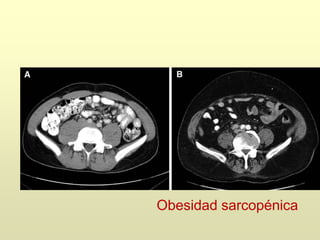

ADT

Osteoporosis y

aumento fracturas

Alteración composición

corporal:

Obesidad sarcopénica

1.- Los aLH-RH incrementan la masa grasa

y disminuyen la masa muscular